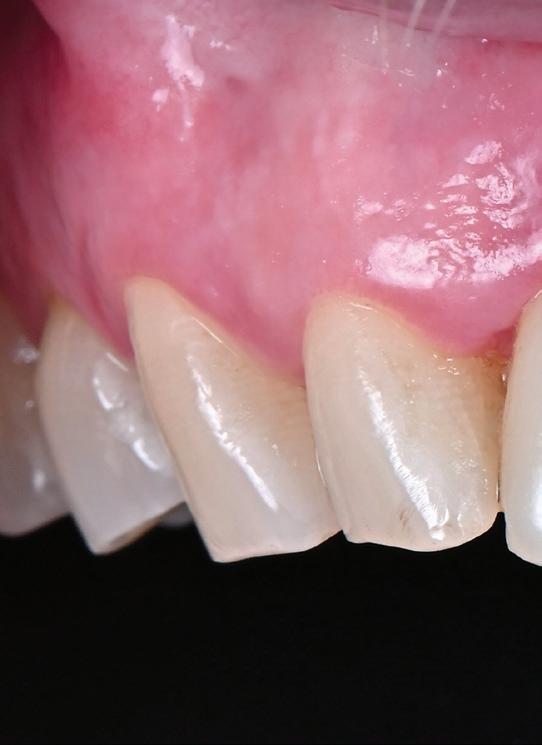

Trebuie remarcat, totuși, că în cazul implanturilor ceramice, ca și în al celor de titan, cementita, adică inflamația periimplantară cauzată de reziduurile de ciment, poate duce la periimplantită. În plus, la implanturile din dioxid de zirconiu poate apărea supraîncălzirea la înșurubarea implantului în os, iar suprafețele excesiv de aspre sau poroase ale implantului pot cauza defecte osoase periimplantare din cauza termoconductivității reduse a materialului. Deși sunt necesare mai multe dovezi științifice care să demonstreze o tendință mai scăzută spre periimplantită în cazul implanturilor ceramice, argumentul esențial pentru aceste implanturi bazat pe experiența clinică este starea excelentă și aproape constant lipsită de inflamație a țesuturilor moi periimplantare (fig. 3).

În plus, aceste proprietăți bioinerte par să aibă și beneficii în ceea ce privește dezvoltarea periimplantitei și calitatea țesuturilor moi. În comparație cu titanul, dioxidul de zirconiu prezintă acumulare de placă și aderență bacteriană mai redusă, precum și o grosime mai mică a biofilmului depus. Și fluxul sanguin circulant către țesuturile moi este mai asemănător cu cel al unui dinte natural în cazul ceramicii față de titan, care oferă flux sanguin redus semnificativ. Se știe că o circulație sanguină mai bună înseamnă țesuturi moi mai sănătoase, care, la rândul lor, prezintă rezultate estetice îmbunătățite. Deși deocamdată lipsesc dovezile pe termen lung pentru implanturile ceramice, sunt disponibile rezultatele inițiale la 3 și 5 ani, iar tendința, susținută de studii preclinice și experiența clinică, este că dioxidul de zirconiu demonstrează același rezultat - iar în unele studii chiar o pierdere osoasă marginală mai redusă față de implanturile de titan. În această perioadă încă nu s-a descris clinic periimplantită.

RECONSTITUIREA țesuturilor moi periimplantare. Scopul acestui raport de caz este de a demonstra procedurile chirurgicale utilizate pentru corectarea unui defect al țesuturilor moi periimplantare folosind țesutul moale interdentar în combinație cu tuberozitatea ca locație donatoare de țesut conjunctiv, utilizând o abordare prin tunelizare într-o zonă estetică.